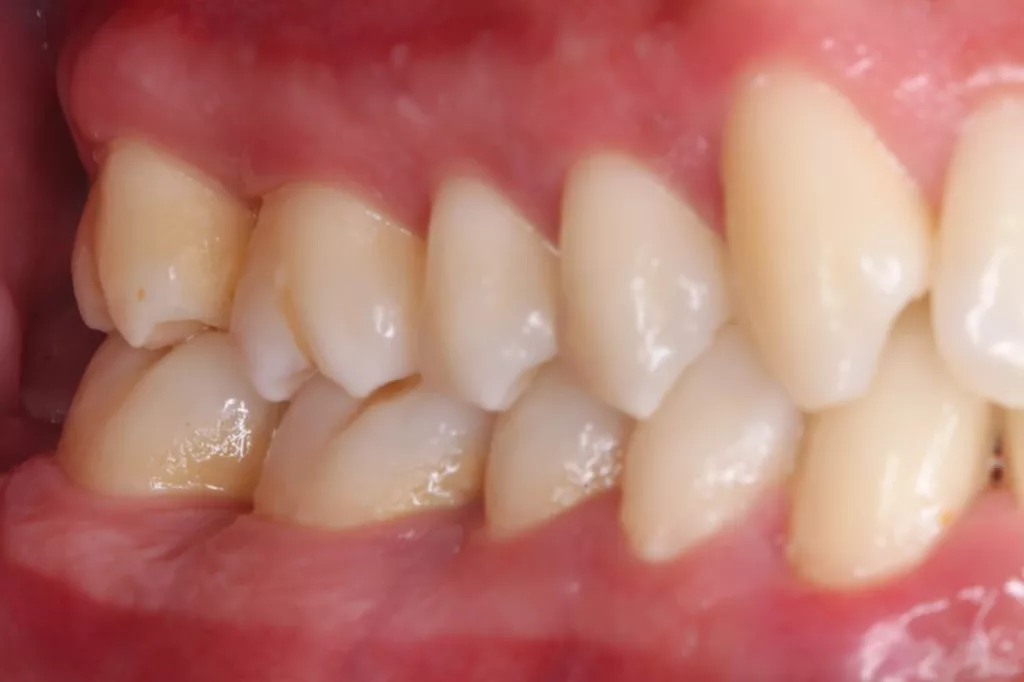

Robuste Evidenz aus aktuellen großen bevölkerungsbasierten Studien zeigt eine Überlegenheit der Effektivität elektrischer Zahnbürsten gegenüber Handzahnbürsten. Darüber hinaus legen systematische Übersichtsarbeiten und In-vitro-Studien einen zusätzlichen Effekt – die Putzwirkung auch ohne direkten Borstenkontakt durch unterschiedliche Strömungsphänomene – bestimmter elektrischer Zahnbürsten (Schallzahnbürsten) nahe. Laboruntersuchungen zeigen aber auch große Unterschiede der untersuchten Zahnbürsten hinsichtlich der Effektivität der Biofilmreduktion. Das bedeutet, dass in der Klinik (Abb. 7–9) in aller Regel eine Empfehlung für elektrische Zahnbürsten und (!) geeignete Hilfsmittel für die Zahnzwischenraumpflege vorliegen sollte.